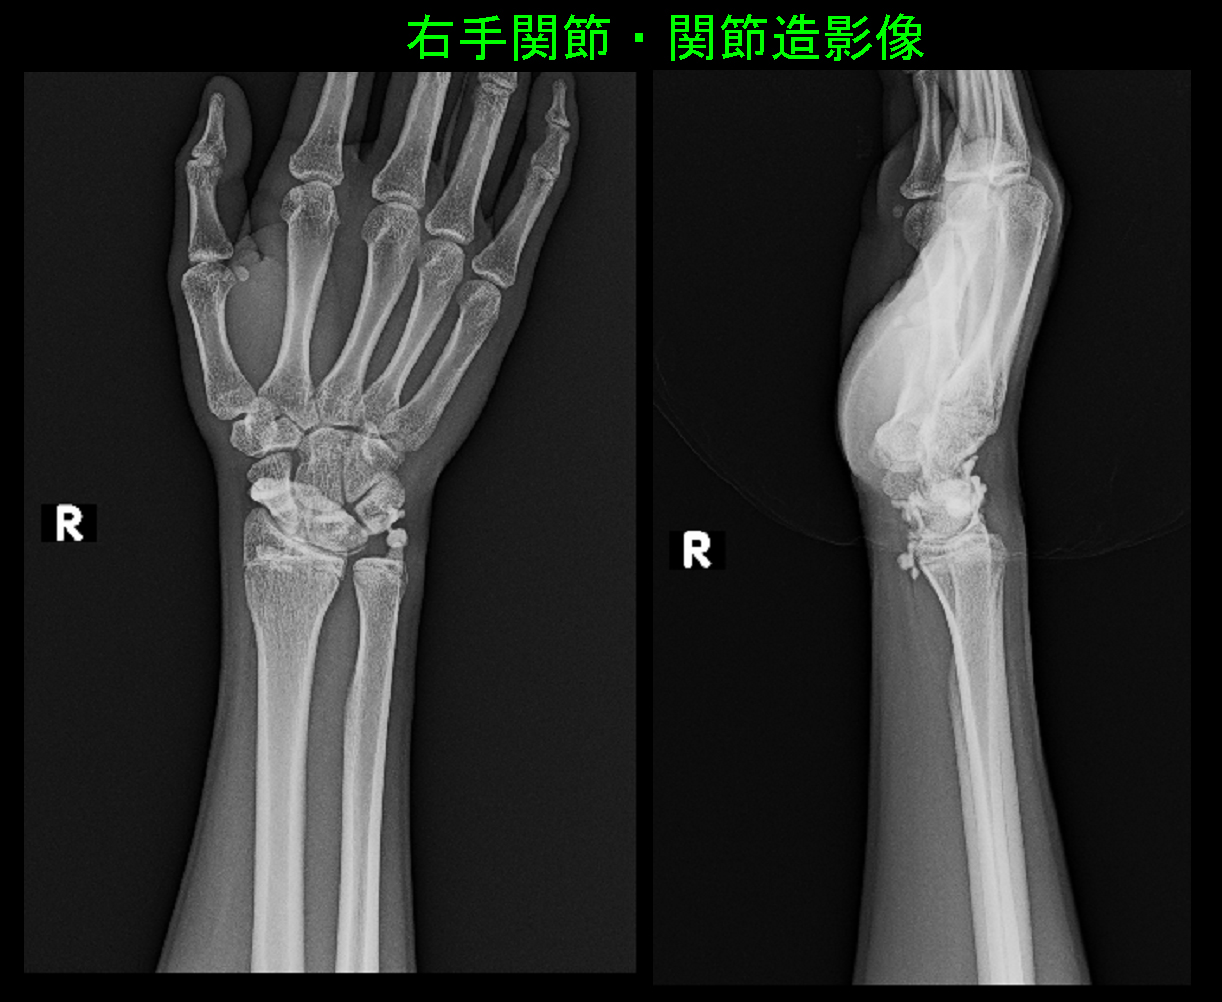

24才女 Xp.jpg

ドアノブを回す、立ち上がりに左手をつくと痛いということでした。左手関節部では赤矢印の三角線維軟骨部に圧痛(押すと痛むという所見)を認めました。レントゲン像は異常がありません。